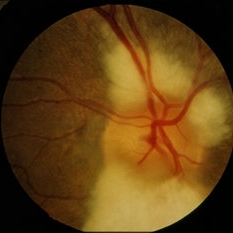

Myelinated Nerve Fiber Layer

Jan 30 2015 by H. Michael Lambert, MD

Myelin of optic nerve head covering optic nerve grossly.

Condition/keywords: myelinated nerve fiber layer